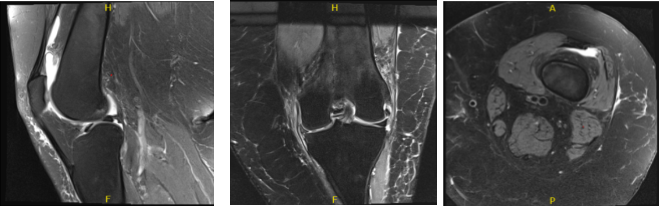

MRIs were reviewed and discussed by the doctor; There is no acute fracture or osteonecrosis. Moderate medial collateral ligament sprain/partial tear is likely reactive. The cruciate and collateral ligaments are otherwise within normal limits.

The lateral meniscus is intact. Focal full-thickness cartilage fissuring is identified in the posterior lateral tibial plateau with mild subchondral edema. There is increased intrasubstance signal abnormality within the body and posterior horn of the medial meniscus with an incomplete radial tear at the body-posterior horn junction.

No displaced fragment is seen. The posterior root attachment is intact. There is moderate thinning of the central weight bearing cartilage. Patellofemoral compartment: There is patella alta and lateral patellar tilt. Softening of the patellar cartilage is noted without full-thickness defect.

Faint edema within the lateral head gastrocnemius muscle may reflect mild strain. No high-grade disproportionate muscle atrophy is seen. The imaged tendons, inclusive of the extensor mechanism, are intact. There is a small joint effusion. No popliteal cyst is appreciated.

There are no intra-articular ossific loose bodies. Subcutaneous edema is nonspecific, the neurovascular structures demonstrate normal course. Medial meniscus tear and medial collateral ligament sprain/tear. Elsewhere most pronounced in the medial compartment. Small joint effusion.

MRI Left Knee non-contrast